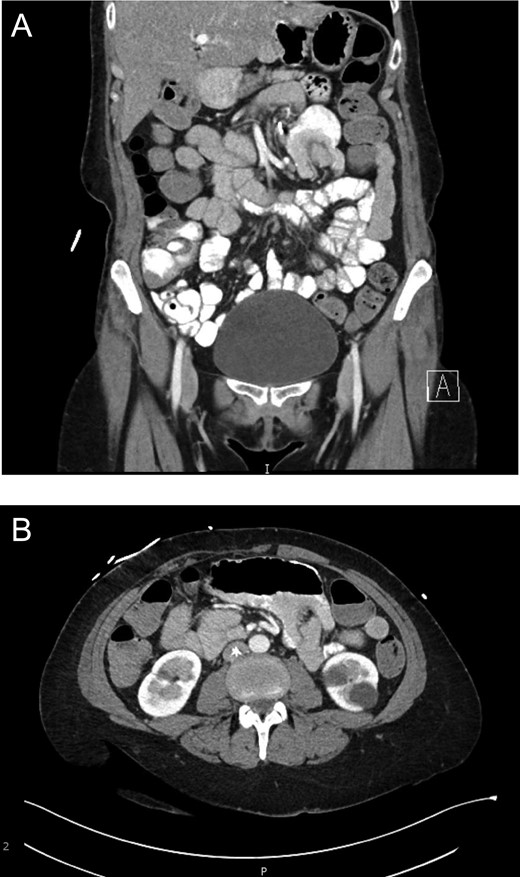

A 47-year-old female presented seven years after RYGB complaining of 4-month history of intermittent abdominal pain, abdominal distention, and belching. Eventual workup included CT scan (Fig. 1) with intravenous and oral contrast demonstrating retrograde intussusception of the common limb into the enteroenteric anastomosis.

(a) Evidence of intussusception on CT scan (Coronal View). Demonstration of intussusception at the Roux-en-Y enteroenteric anastomosis. (b) Evidence of intussusception on CT scan (Transverse View). Demonstration of intussusception at the Roux-en-Y enteroenteric anastomosis.